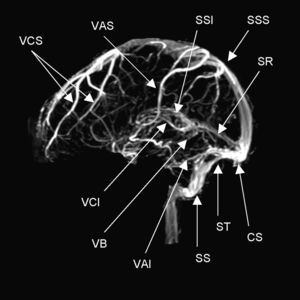

AnatomíaEl drenaje venoso del cerebro se realiza por un sistema venoso superficial y otro profundo que drena hacia los principales senos durales: seno sagital superior (SSS), seno sagital inferior (SSI), senos laterales (SL), seno cavernoso y seno recto (fig. 1). El drenaje final se realiza a través de la vena yugular interna. Las venas del sistema venoso superficial, que drenan principalmente al SSS y a los SL, cuentan con numerosas anastomosis y en casos de oclusión son de difícil diagnóstico. El sistema venoso profundo drena sangre desde la sustancia blanca profunda de los hemisferios y los ganglios basales en la vena de Galeno. Tanto el sistema venoso superficial como el profundo tienen múltiples anastomosis. Lo anterior permite que el drenaje venoso tome vías alternas de acuerdo con diferentes necesidades, como en el caso de una trombosis4,5.

Anatomía normal de los principales senos venosos en imagen por resonancia magnética en fase venosa. CS: confluencia de los senos (presa de Herófilo); VAI: vena anastomótica inferior (de Labbé); VAS: vena anastomótica superior (de Trolard); VB: vena basal (de Rosenthal); VCI: vena cerebral interna (de Galeno); VCS: venas cerebrales superficiales; SR: seno recto;SS: seno sigmoideo; SSI: seno sagital inferior; SSS: seno sagital superior; ST: seno transverso o lateral.

Existen dos grupos de senos durales, el posterosuperior y el anteroinferior. El grupo posterosuperior comprende el SSS, el SSI, los SL con sus porciones transversa y sigmoidea, el seno recto y el seno occipital. El grupo anteroinferior incluye los senos petrosos superior e inferior y el cavernoso. Los senos venosos durales tienen un papel importante en la absorción del líquido cefalorraquídeo (LCR), ya que contienen las vellosidades aracnoideas.

El SSS drena la mayor parte de la corteza cerebral y corresponde anatómicamente al borde de la hoz del cerebro. Los SL se originan en la presa de Herófilo y se extienden hasta el bulbo de la yugular, tienen una porción transversa y una porción sigmoidea que va unida a la apófisis mastoides y es susceptible de trombosis en pacientes con mastoiditis u otitis media. El seno lateral drena sangre del cerebelo, tallo encefálico y la parte posterior de los hemisferios cerebrales.

Los senos cavernosos se localizan en la base del cráneo, en posición superolateral a los senos esfenoidales. Por sus paredes laterales discurren los nervios motor ocular común (III), troclear (IV) y las ramas oftálmica y maxilar del trigémino (V). En su parte medial se encuentra el nervio motor ocular externo (VI) y la arteria carótida interna rodeada por su plexo simpático. Los senos cavernosos drenan a las venas yugulares internas a través de los senos petrosos7.